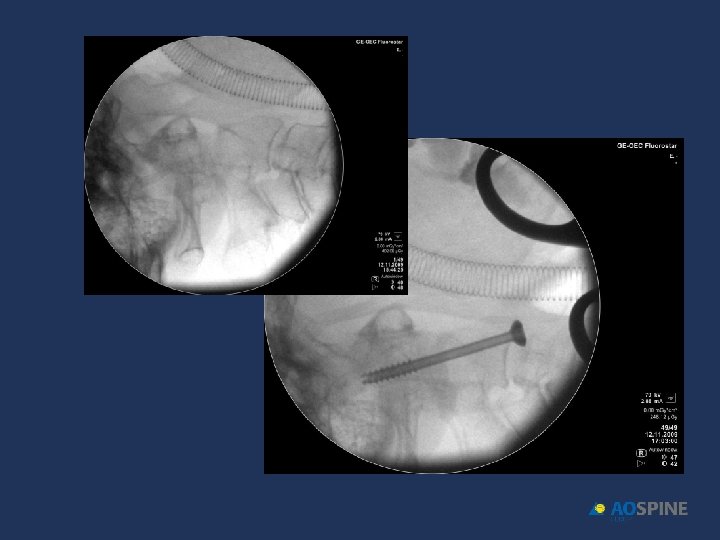

ODONTOID FRACTURES odontoid screw ADVANTAGES CONTRAINDICATIONS • PRESERVES MOTION C 1 C 2 • TRANSVERSE LIG RUPTURE • DONT NEED POSTOP HALO • EXTENSE C 2 BODY FX • DONT NEED BONE GRAFT • IRREDUCTIBLE FRACTURE • ANTERIOR OBLICUE FX

ODONTOID FRACTURES • RIGID COLLAR 10 -12 WEEKS • ONE SCREW • BEST RESULTS DURING FIRST 6 MONTHS AFTER FX Jenkins et al. J Neurosurg 1988, 89 Apfelbaum et al. J Neurosurg 2002, 93

ODONTOID FRACTURES odontoid screw • 90% FUSION TYPE II • 95% FUSION TYPE II < 6 MONTHS EVOL. • 100% FUSION TYPE III